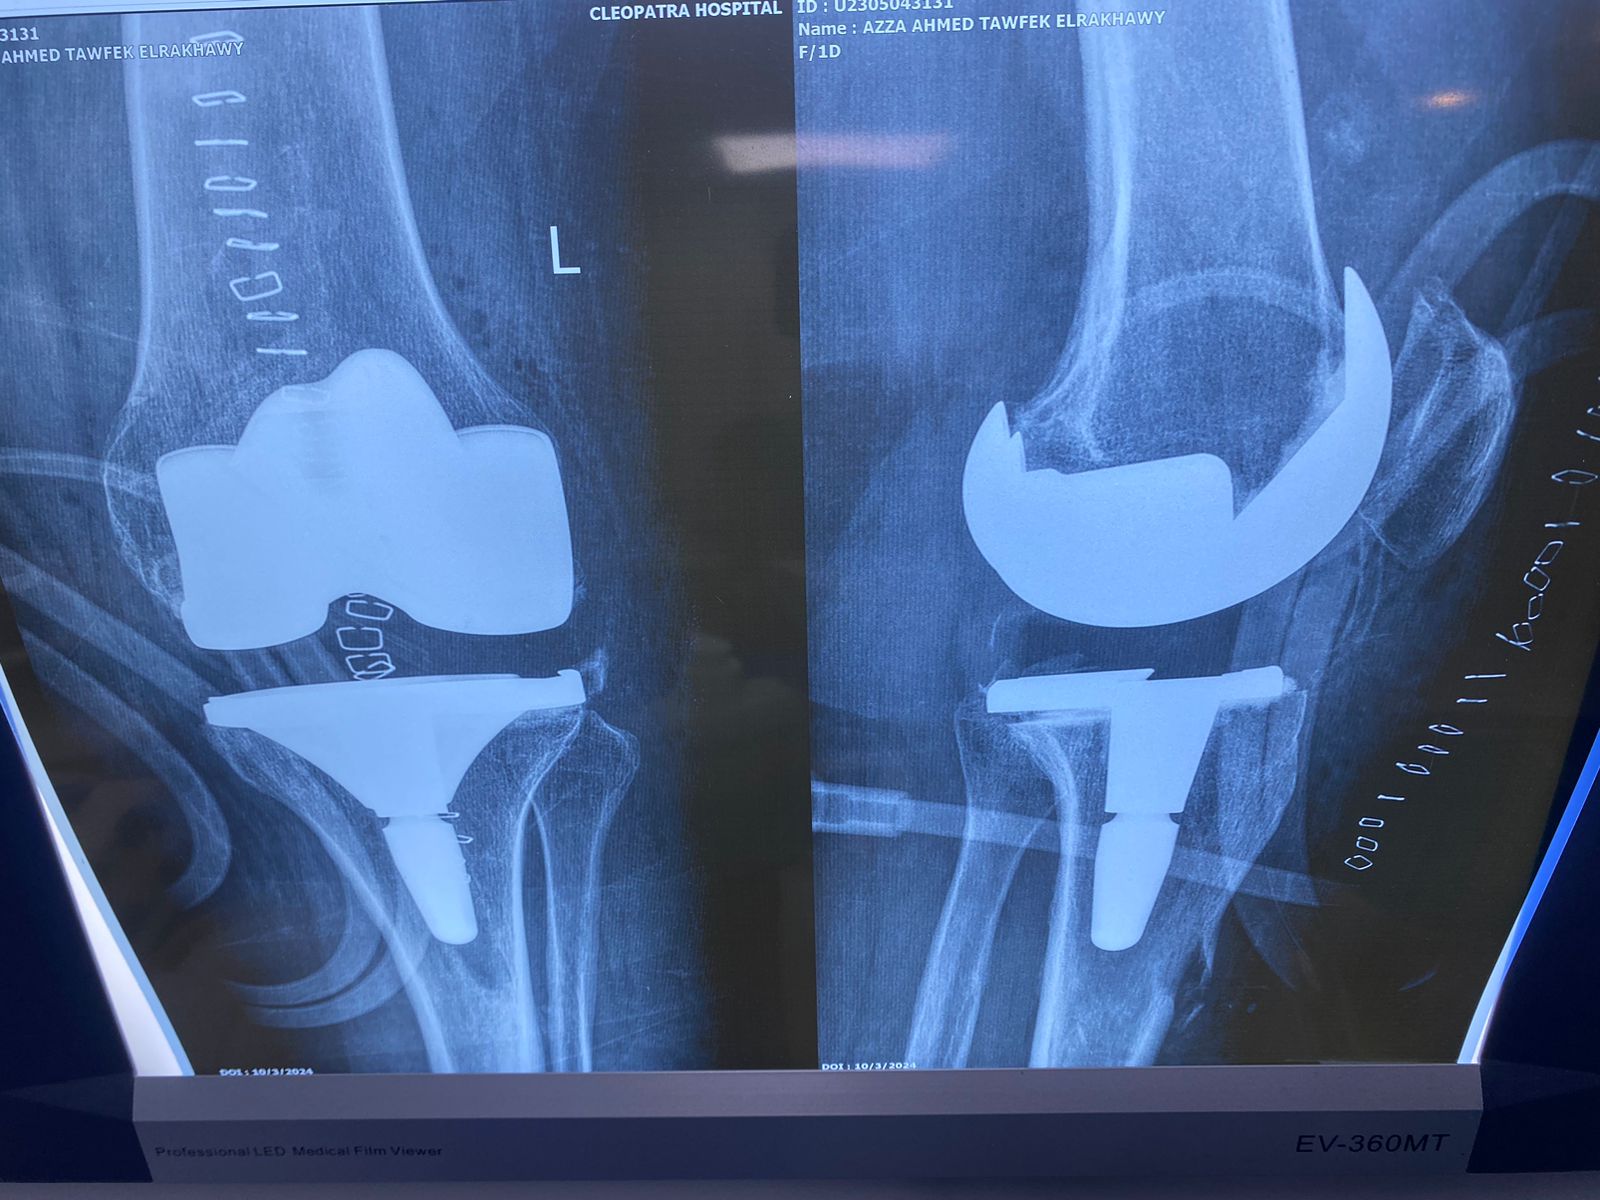

السيده/ عزه الرخاوي العمر ٦٨ عام كانت تعاني من تآكل شديد بالركبتين تم تغيير المفصل الايسر منذ ٣ أعوام تم تغيير المفصل الايمن منذ ٨ اشهر هي الآن تمشي بشكل طبيعي تماما